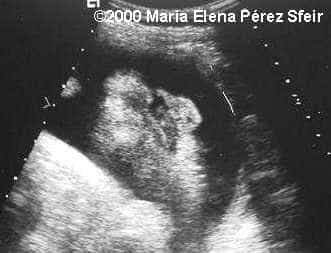

Cleft-lip, unilateral MarÃa Elena Pérez Sfeir, MD Article Published: May 30, 2002 Patagonia, Argentina This is an example of cleft-lip in a 3rd trimester fetus. Discussion Board Start a discussion about this article Add to Favorites Favorite